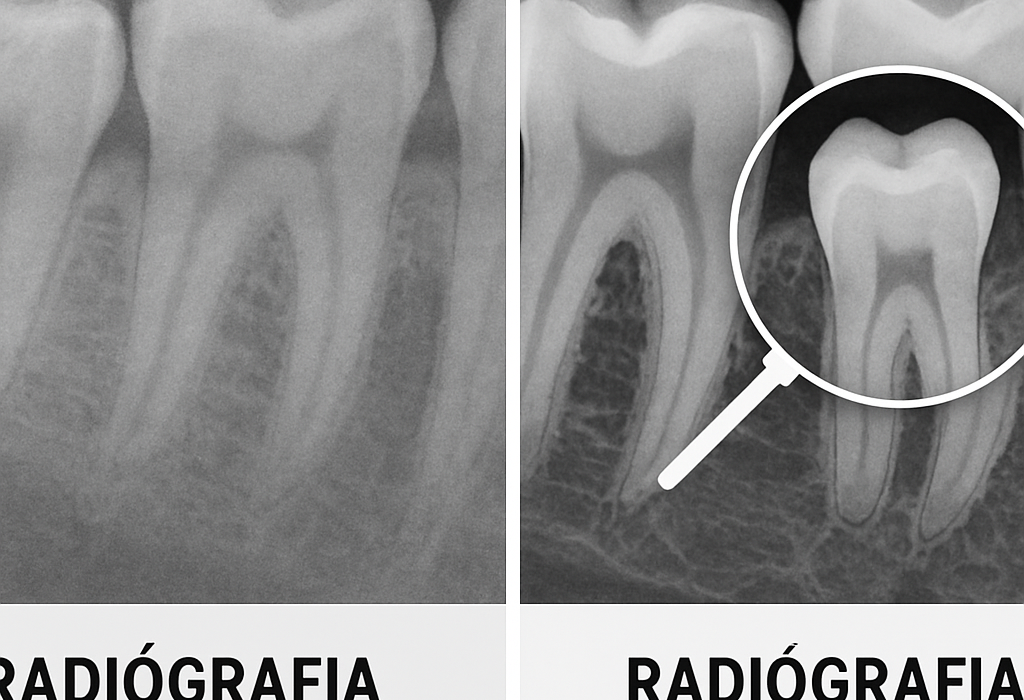

Uno de los pilares de este enfoque es el diagnóstico por imagen. La radiografía panorámica digital, por ejemplo, sigue siendo una herramienta muy utilizada para la primera valoración porque permite observar de manera global dientes, hueso y estructuras relevantes. En su versión digital, facilita la visualización, el almacenamiento y la comunicación clínica. Para pacientes que quieren informarse antes de su cita, La Clínica Dental publicó una guía práctica sobre el tema: https://laclinicadental.org/rayos-x-panoramicos-digitales-vs-convencionales-beneficios-y-como-funcionan/.